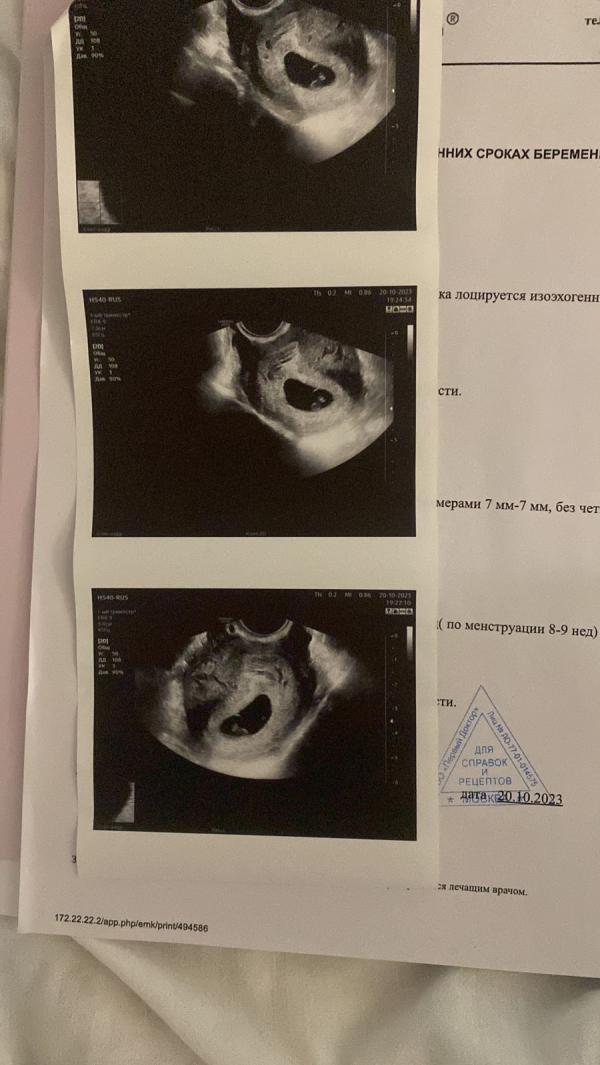

post image 1

post image 2

post image 3

22.10 Вот и закончилась моя Беременость на 8 неделях пусть останется здесь 😔